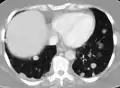

![]() | |

Illustration showing hematogenous metastasis | |